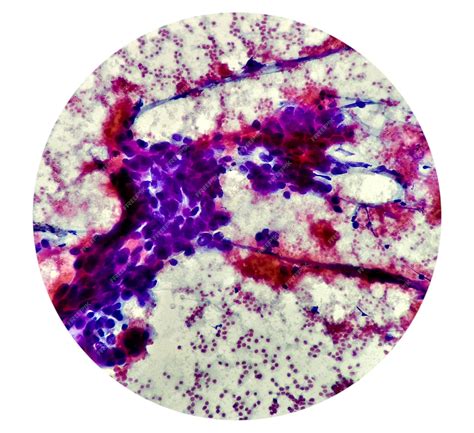

• Biopsy: A sample of the tumor tissue is removed and examined under a microscope to confirm the diagnosis and determine the specific subtype of Spindle Cell Sarcoma.